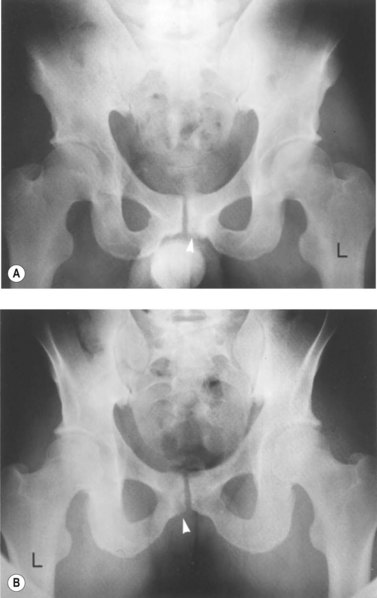

With osteitis pubis no instability of the pubic symphysis occurs, but there is tenderness over the area with rarefaction of the pubic bones and sometimes widening of the symphysis pubis apparent on x-ray. Erosion of the superior and inferior aspects of the symphysis may also occur (Fig. 8.13). The athlete often has a waddling gait, and may describe occasional crepitus. Severe (long-term) cases may progress to sclerosis and eventual narrowing of the symphysial joint space requiring wedge resection (Grace, Shives and Coventry, 1989). Bone marrow oedema may be visible on MRI scan.

image

Figure 8.13 Osteitis pubis. (A) Anterior and (B) posterior view showing bone fragment.

From Magee (2002) with permission.

Palpation may be used to differentiate true osteitis pubis from tendinitis of the gracilis or avulsion injury to the gracilis attachment. The gracilis muscle attaches to the inferior aspect of the symphysis and local palpation may reveal spot tenderness (Fig. 8.14). Both of these conditions give pain to resisted adduction as well as to local palpation. Importantly, osteitis pubis often gives pain to pelvic springing tests to the iliac crest whilst gracilis conditions do not. The condition may be graded as illustrated in Table 8.4.